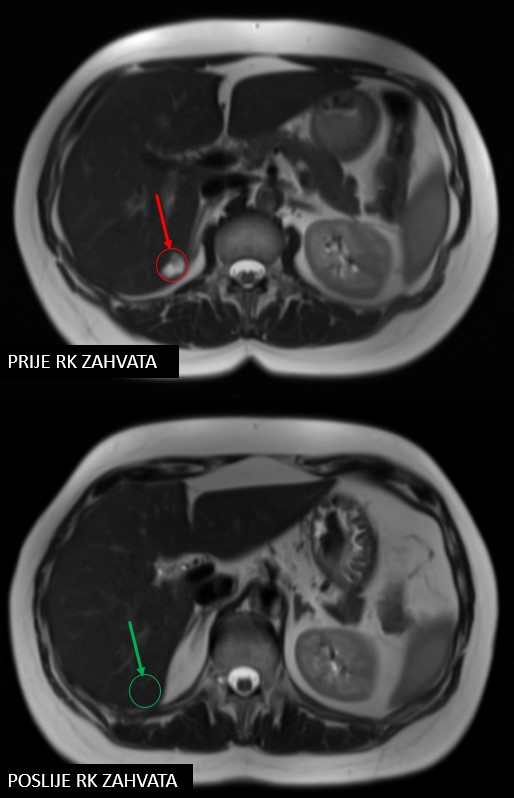

Rezultat – 47 mjeseci nakon RK

potpuni nestanak tretiranih lezija